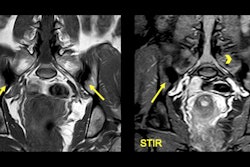

When it comes to suspected cases of axial spondyloarthritis, MRI can be of particular value. Spanish researchers have shared their experiences with us of this painful, chronic form of arthritis that mainly affects the joints of the spine and tends to present in young people in the form of chronic back pain. Find out more in today's special feature article.